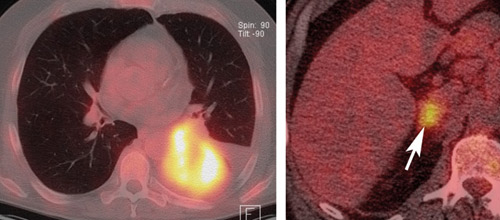

En 57 år gammel mann med adenokarsinom i venstre lunges underlapp ble undersøkt med 18F-fluoro-2-deoksyglukose (FDG)-PET kombinert med CT i samme seanse for stadieinndeling av tumoren. FDG er det vanligste sporstoffet som benyttes i PET og akkumuleres gjennom en sukkerforbrenningsprosess i cellene og gjenspeiler cellenes energibehov.

Bildet til venstre viser høyt opptak i tumor (gul/hvitt), men det er ikke innvekst i mediastinum eller store kar, slik at tumoren i seg selv er operabel.